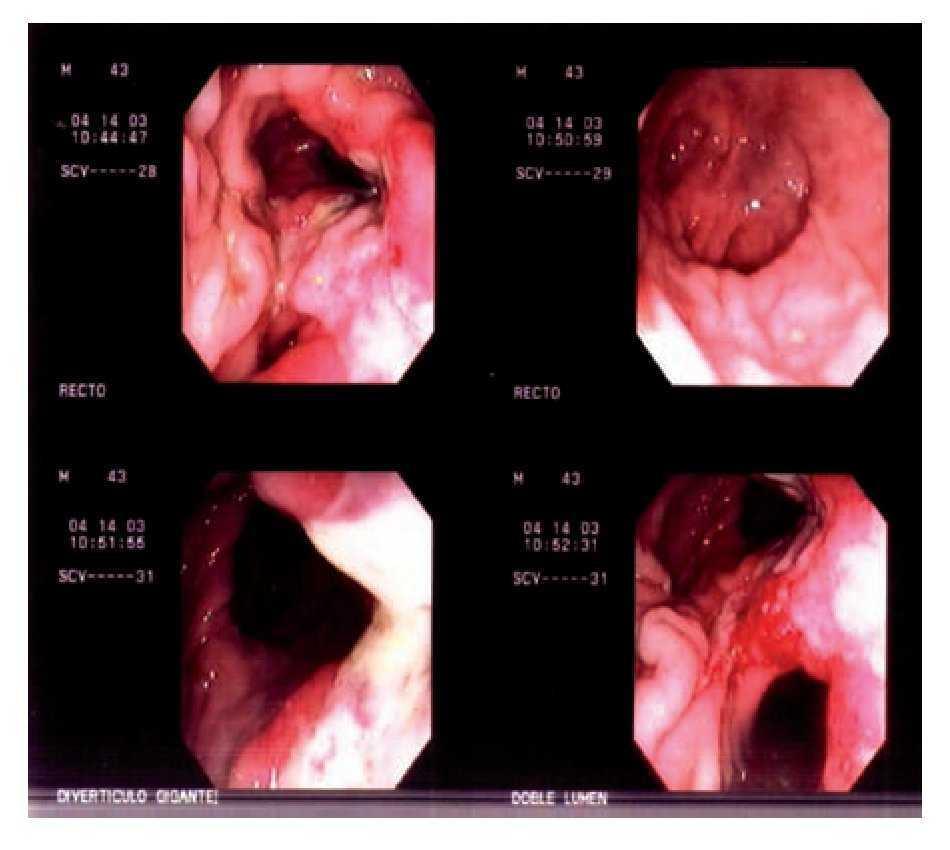

Paciente masculino de 43 años de edad, quien acude a urgencias del Hospital Escandón de Tacubaya, México, D.F., abril del 2003 por datos de estreñimiento crónico, dolor anorrectal intenso, tenesmo, sangrado transrectal escaso e imposibilidad para la defecación. Al examen físico mostraba fascie dolorosa, dolor abdominal sin datos de irritación peritoneal, abdomen distendido y al tacto rectal masa grande, la radiografía simple de abdomen mostró datos de impactación fecal importante, se realiza la desimpactación mecánica bajo sedación, luego mediante rectosigmoidoscopia (RSC) rígida se logra detectar doble lumen rectal (anterior y posterior) por encima del anillo anorrectal con úlcera fibrosa de aspecto nacarado fibrinoide de aproximadamente 3 cm de longitud por 1 cm de ancho, sobre la base del septum que separa ambos lúmenes (Imagen 1), sitio de donde se toman biopsias, posteriormente se realiza colon por enema con material hidrosoluble (Imagen 2) y se realiza colonoscopia sin encontrar patología asociada, se toman biopsias en mucosa del fondo del saco atrófico, no detectando ectopia gástrica ni displasia. Se plantea al paciente tratamiento quirúrgico; resección de saco con anastomosis coloanal a efecto de evitar nueva obstrucción intestinal a futuro, pero cuando se le informa al paciente la pequeña posibilidad del riesgo de lesión de fibras nerviosas entre las posibles complicaciones posoperatorias, se rehúsa completamente a cualquier opción quirúrgica y dado que con dieta rica en fibra notó mejoría sintomática importante sin obstrucción hasta la fecha (contacto telefónico, ya que el paciente por su propia voluntad interrumpió el seguimiento hospitalario).

Imagen 1. Rectosigmoidoscopia